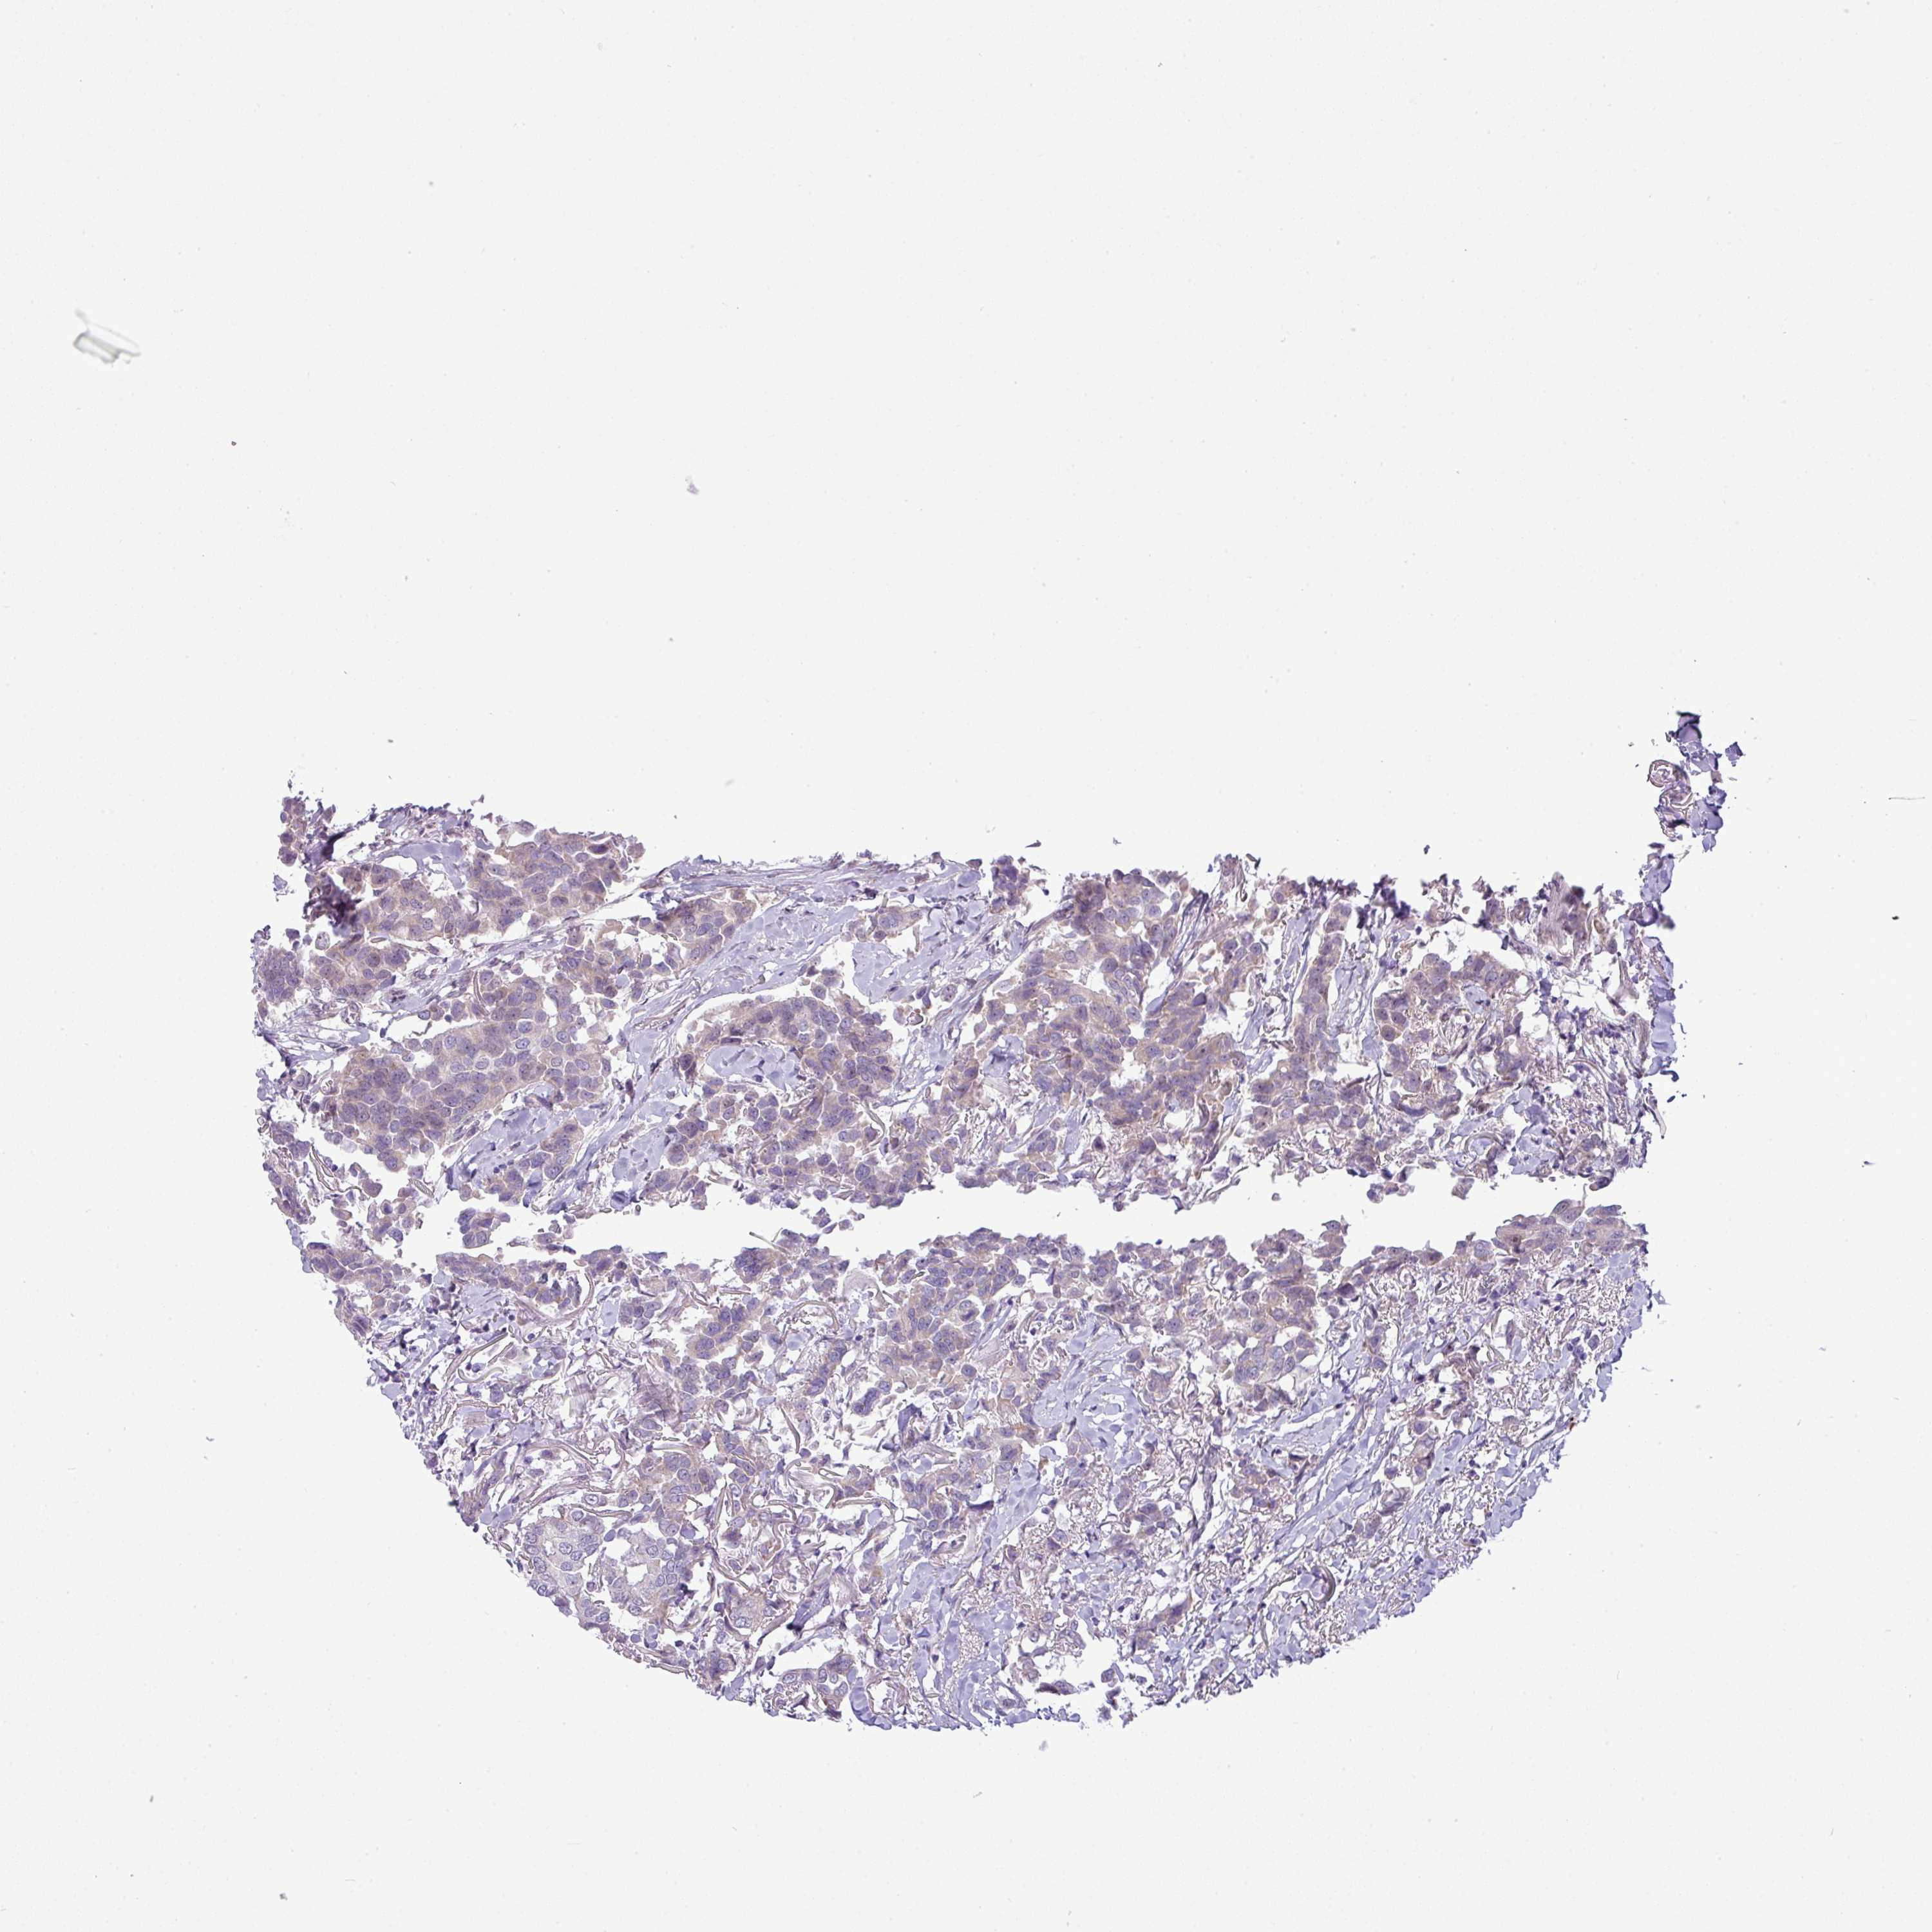

CANCER BREAST CANCER Show tissue menu

BRCA TCGA BRCA VALIDATION PROTEIN EXPRESSION